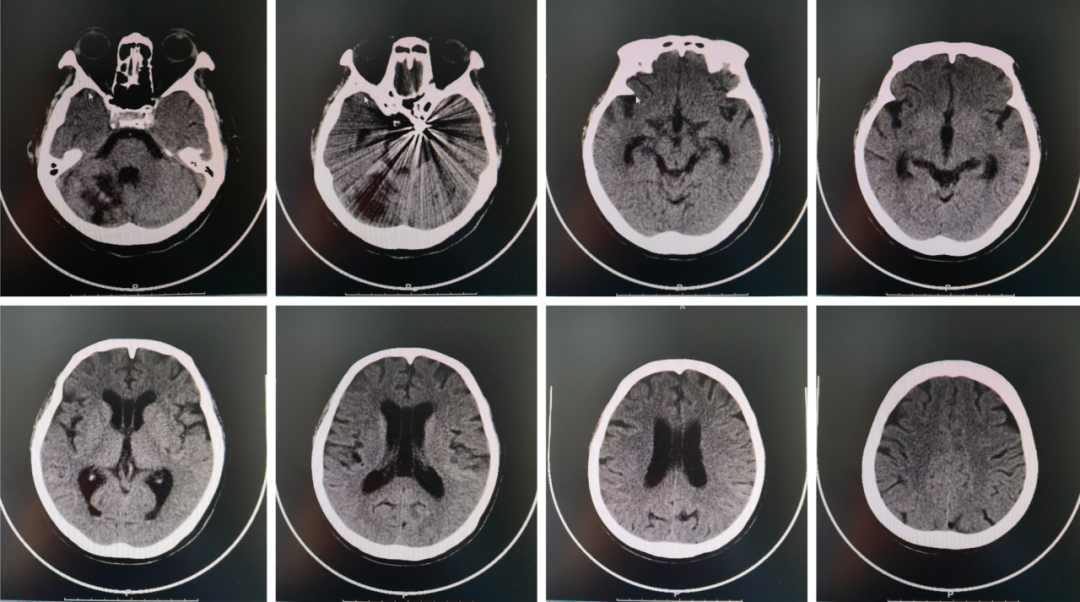

术后颅脑CT示:颅内动脉瘤栓塞术后改变,右侧小脑半球软化灶。